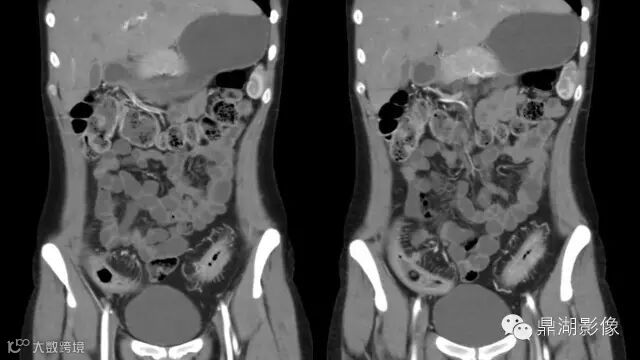

Crohn's disease.

IBD,CD

the answer is easy,but today we will learn this diease deeply

The comb sign refers to the hypervascular appearance of the mesentery in active Crohn disease.

It is the comb sign the most specific sign for crohn's disease.